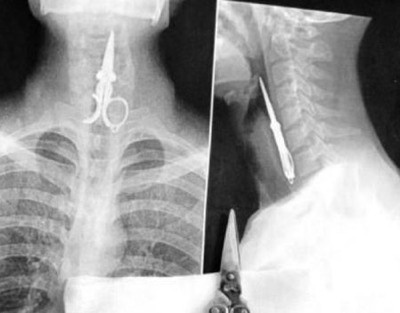

![]() |

| Họ cũng không thể hiểu tại sao chiếc kéo sắc nhọn lại có thể xuất hiện trong cổ họng của một người đàn ông. |